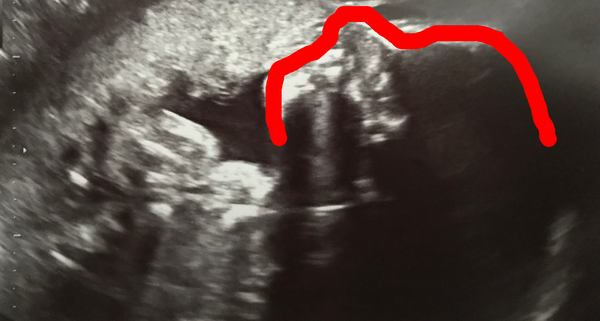

Gem173 · 14/06/2018 06:52

@bertiebotts, I’ve drawn an outline of roughly where his face is. Look at this and then look at the original and you might see it better xx

August 2018 #5